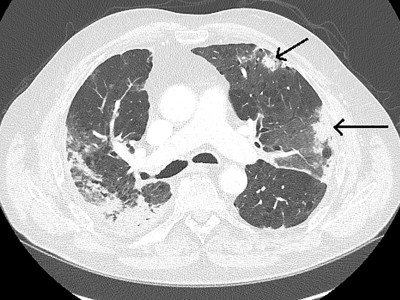

Der besondere Fall: Hyponatriämie bei einer 58-Jährigen mit Lungenkarzinom

Manche Patienten mit nichtkleinzelligem Lungenkarzinom erfahren bei Progress unter zielgerichteter Therapie eine Tumortransformation. Dann ist es nötig, erneut zu biopsieren – so wie im folgenden Fall.

Hyponatriämie bei einem EGFR-positiven pulmonalen Adenokarzinom

Die Patientin entwickelte unter einer Tyrosinkinaseinhibitor-Therapie eine schwere Hyponatriämie – u.a. mit begleitenden Konzentrationsstörungen. Handelt es sich um ein Fortschreiten des Tumors, eine Nebenwirkung der Therapie oder um etwas Anderes?

Kind erhält Leukämie Therapie/© FatCamera / Getty Images / iStock (Symbolbild mit Fotomodell), Immuncheckpointinhibitoren binden an Krebszelloberflächenproteine /© Juan Gärtner / stock.adobe.com, Arzt misst Blutzucker per Glucometer/© geargodz / Stock.adobe.com (Symbolbild mit Fotomodell), CT der Lunge mit Konsolidierungen (Pfeile) und Milchglastrübungen bei einer immunvermittelten Pneumonitis/© Minuth-Fuchs, K.L., Schulz, C. / all rights reserved Springer Medizin Verlag GmbH, Hepatozelluläres Karzinom im Lebersegment VIII/© Wengert, G. et al. / all rights reserved Springer Medizin Verlag GmbH, Blutabstrich der chonisch lymphatischen Leukämie/© jarun011 / Getty Images / iStock, Endobronchialer Befund mit exophytischem Tumor im Bereich des rechten Oberlappens/© Möller, M., Schütte, W. / all rights reserved Springer Medizin Verlag GmbH, Mann nimmt eine Tablette ein/© Jelena Stanojkovic / stock.adobe.com (Symbolbild mit Fotomodell), Thymom mit pleuraler Aussaat rechts im Masaoka-Koga-Stadium IVa./© Ried, M. et al. / all rights reserved Springer Medizin Verlag GmbH, Patientin schaut besorgt auf Infusionsbeutel/© KatarzynaBialasiewicz / Getty Images / iStock (Symbolbild mit Fotomodellen), Ältere Frau nimmt Tablette ein/© amenic181 / stock.adobe.com (Symbolbild mit Fotomodell), Generalisierte, konfluierende, kokardenartige Erytheme mit zentraler Blase/© Springer Medizin Verlag GmbH, Bronchialkarzinom/© Dr. Myriam Koch , Pulmonales Adenokarzinom bei Diagnosestellung/© Springer Medizin, Bestrahlung eines Lungenkarzinoms/© Springer Medizin Verlag GmbH, Search Icon, Ältere Frau fasst sich an die Brust/© Jelena Stanojkovic / Stock.adobe.com (Symbolbild mit Fotomodell), Person setzt DNS-Probe in Maschine ein/© Vit Kovalcik / stock.adobe.com, Mann raucht Joint/© Daniel Sierralta / Westend61 / stock.adobe.com (Symbolbild mit Fotomodell), Blut in Toilette/© stylefoto24 / stock.adobe.com